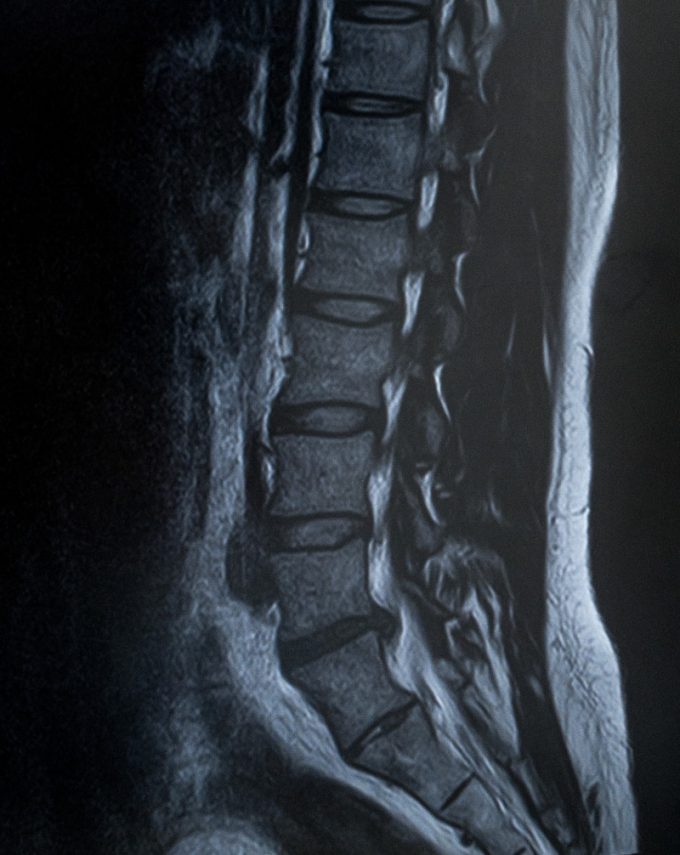

椎間板ヘルニア

椎間板ヘルニア入院体験記その1: 検査入院初日。ミエログラフィー検査結果報告。

椎間板ヘルニア検査入院 ミエログラフィー検査は痛いのか 35才にもなって注射が大の苦手。痛みにメチャ弱いトホホなオッサンがミエログラフィー検査が果たしてどれだけ痛いかおよび、人生初の入院初日をレポートする。 2012年7月12日(木) いよいよヘルニ... -